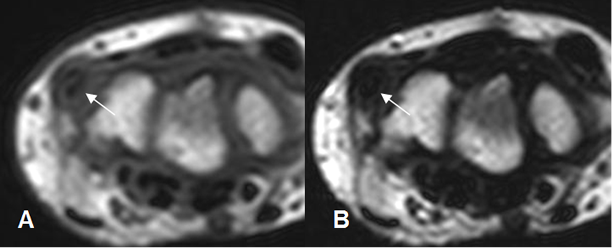

En la RM, los hallazgos son similares a la ecografía. Engrosamiento del tendón y alteración de su SI por tendinitis y presencia de liquido a su alrededor, por tenosinovitis. (Fig 90 a 93).

Fig 91. Tendinitis

A: RM axial en T1 y B: RM axial en T2. Engrosamiento y alteración de la SI intrasustancia del flexor ulnar del carpo, por tendinitis.